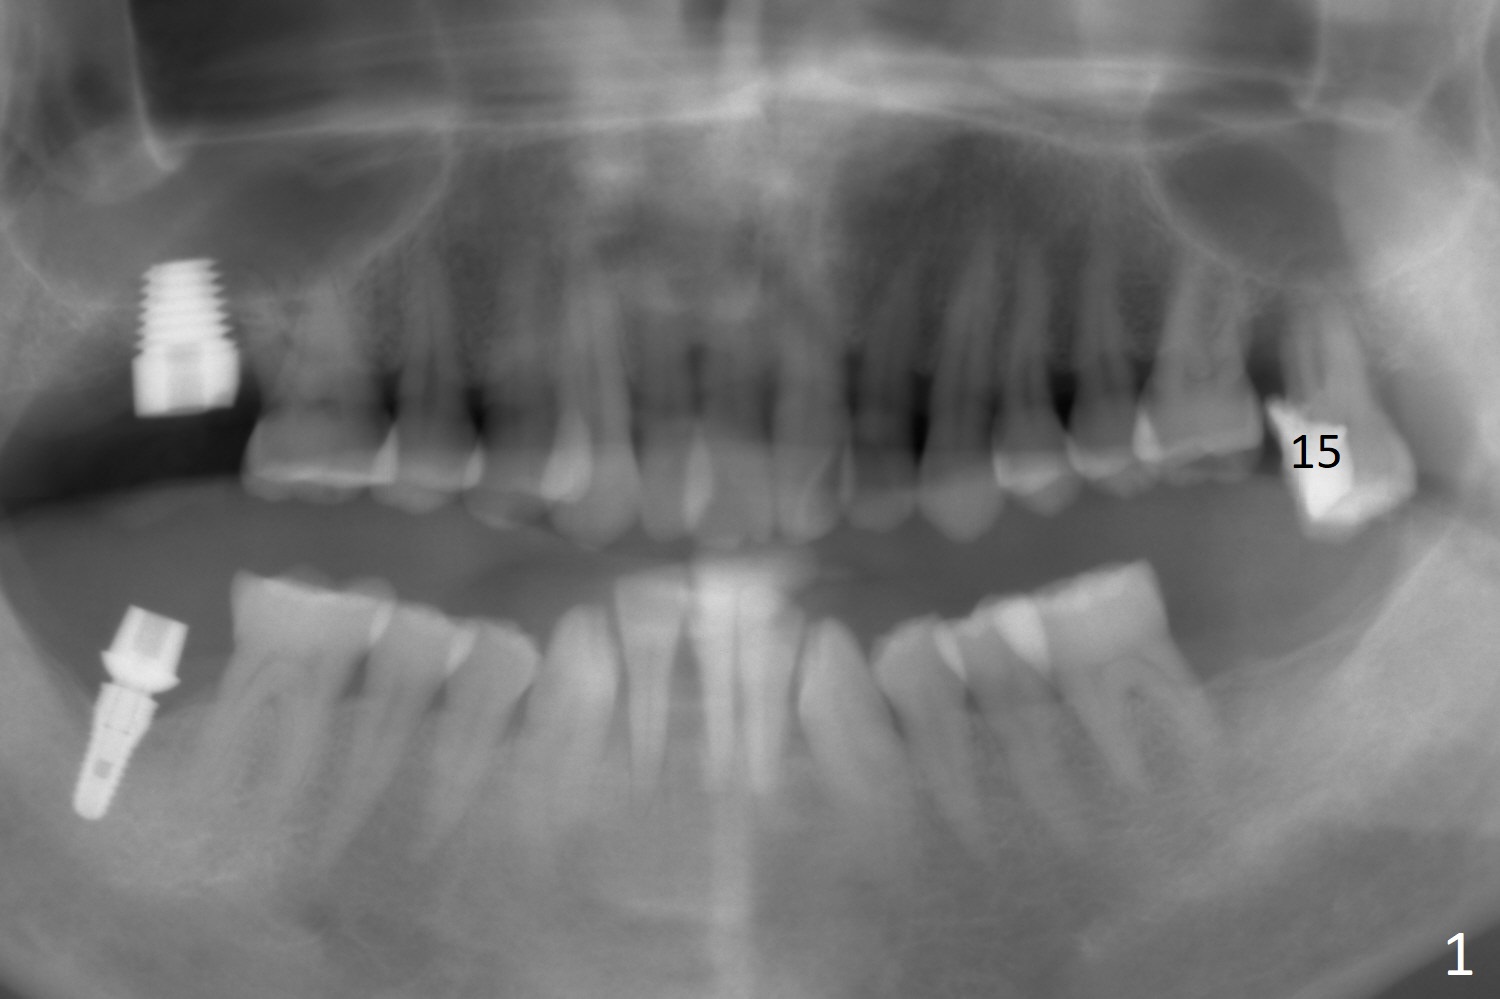

A 47-year-old man will return for #15 extraction and implant (Fig.1). Bone loss seems to be the most severe around the mesiobuccal root (Fig.2 *), from which the osteotomy should stay away (Fig.3). Take PVS impression for the sockets. Use Tatum osteotomes for sinus lift.